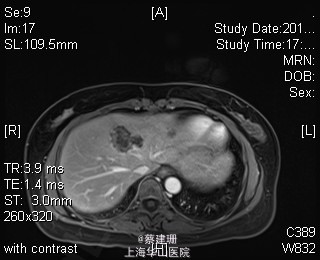

主诉:平滑肌肉瘤、肝转移癌术后,发现肝多发转移2月余。 现病史:患者3年前外院检查发现后腹膜肿瘤,外院行后腹膜肿瘤切除术后,术后病理为:平滑肌肉瘤,2013年12发现肝左叶转移癌,外院行肝左叶肿瘤切除术,术后病理为:梭行平滑肌肉瘤。2月余前患者复查发现肝脏多发转移,2015-4月肝脏MRI:肝脏多发转移。现患者无恶心、呕吐,无呕血、黑便,无皮肤巩膜黄染,无剧烈腹痛发作。现为进一步诊治收住入院。

查体:锁骨上淋巴结未扪及肿大;腹部平坦,可见陈旧性手术疤痕。未见肠型、胃型蠕动波,腹软,无压痛及反跳痛,无肌卫,肝脾肋下未及。Murphy’s 征(-),肝区叩击痛(-),肾区叩击痛(-);移动性浊音阴性。 辅查:2015-4月肝脏MRI:肝脏多发转移。

诊断 :1、多发肝转移癌 2、后腹膜平滑肌肉瘤术后 3、肝转移癌术后 处理:取右侧肋缘下切口,左侧延长,逐层切开进腹,探查腹腔:见上腹部粘连,仔细游离上腹部腹腔粘连,探查见无腹水,胃、肠、胰、脾及盆腔脏器未及异常,腹腔未见明显转移结节;肝脏无硬化。肝门淋巴结无肿大,门静脉主干无栓子。肿瘤多枚,最大两枚位于肝右叶VI段,肿瘤大小约7*6*5cm。V段肿瘤直径约5cm。左内叶肿瘤多枚,直径0.5-4cm,紧贴第一肝门。左外叶肿瘤多枚,直径1-3cm,肿块质韧,边界尚清,有包膜。术中诊断为转移性肝癌,决定行左半肝切除,肝右叶特殊肝段切除。